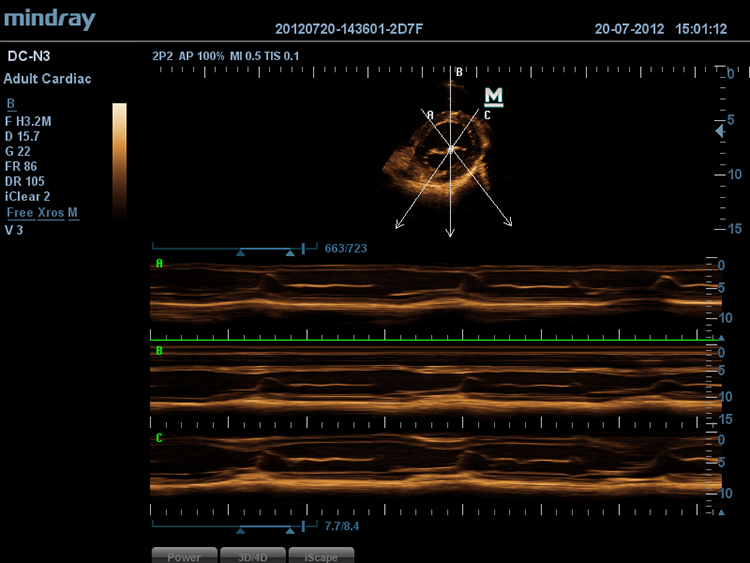

Free Xros MTM

–Я–Њ–Ј–≤–Њ–ї—П–µ—В –њ–Њ–ї—Г—З–Є—В—М —В–Њ—З–љ—Л–µ –∞–љ–∞—В–Њ–Љ–Є—З–µ—Б–Ї–Є–µ –Є–Ј–Љ–µ—А–µ–љ–Є—П –њ–Њ—Б—А–µ–і—Б—В–≤–Њ–Љ —Б–≤–Њ–±–Њ–і–љ–Њ–≥–Њ —А–∞–Ј–Љ–µ—Й–µ–љ–Є—П –ї–Є–љ–Є–є –Ь-—А–µ–ґ–Є–Љ–∞ –њ–Њ–і –ї—О–±—Л–Љ —Г–≥–ї–Њ–Љ. –Ю–њ—В–Є–Љ–∞–ї—М–љ–Њ–µ –Ї–∞—З–µ—Б—В–≤–Њ –Є–Ј–Њ–±—А–∞–ґ–µ–љ–Є—П –і–Њ—Б—В–Є–≥–∞–µ—В—Б—П —Б –њ–Њ–Љ–Њ—Й—М—О –Њ–і–љ–Њ–≤—А–µ–Љ–µ–љ–љ–Њ–≥–Њ –Є—Б–њ–Њ–ї—М–Ј–Њ–≤–∞–љ–Є—П –і–Њ 3 –ї–Є–љ–Є–є –Ь-—А–µ–ґ–Є–Љ–∞.

Free Xros CMTM

–Я–Њ–Ј–≤–Њ–ї—П–µ—В –њ–Њ–ї—Г—З–Є—В—М –њ–Њ–ї–љ—Г—О –Є–љ—Д–Њ—А–Љ–∞—Ж–Є—О –Њ –і–≤–Є–ґ–µ–љ–Є–Є —Б–µ—А–і–µ—З–љ–Њ–є –Љ—Л—И—Ж—Л –≤ —А–∞–Ј–ї–Є—З–љ—Л—Е —Д–∞–Ј–∞—Е —Б–Њ–Ї—А–∞—Й–µ–љ–Є—П –Є –Њ–і–љ–Њ–≤—А–µ–Љ–µ–љ–љ–Њ –Њ–њ—А–µ–і–µ–ї—П—В—М —Б—В–µ–њ–µ–љ—М —Б–Є–љ—Е—А–Њ–љ–Є–Ј–∞—Ж–Є–Є –Љ–Є–Њ–Ї–∞—А–і–∞. –Ґ–Њ—З–љ–Њ—Б—В—М —А–µ–Ј—Г–ї—М—В–∞—В–Њ–≤ –Њ–±–µ—Б–њ–µ—З–Є–≤–∞–µ—В—Б—П –≤—Л—Б–Њ–Ї–Њ–є —З–∞—Б—В–Њ—В–Њ–є –Ї–∞–і—А–Њ–≤.